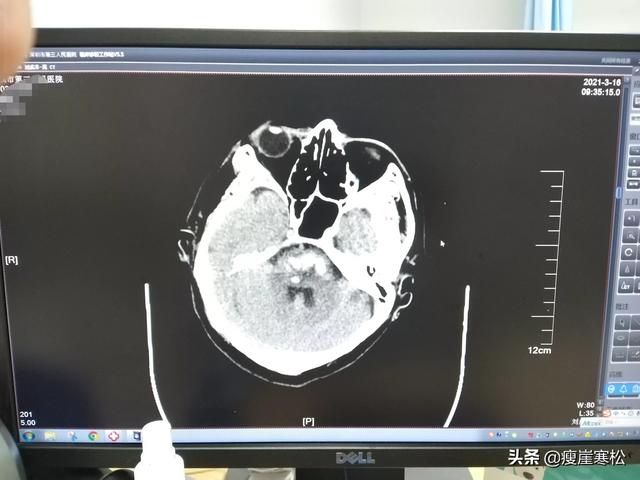

1.激しい頭痛、めまい、嘔吐の後、意識障害。38歳の男性ドライバーが、めまいと嘔吐の後、2時間商品を配達した後、友人に電話して病院に連れて行ってもらい、その後昏睡状態に陥り、脳梗塞を起こした。